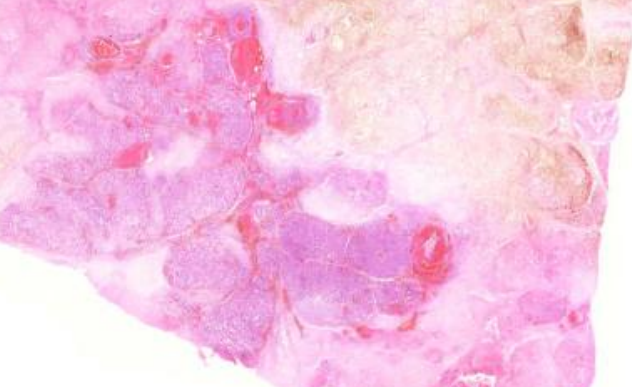

1. Pancreatite aguda necro-hemorrágica (148)

1. Área rosada amorfa

1. Hemorragia

1. Fibrose

2. Presença de PMN nas áreas de necrose

1. Edema

1. Deposição de gordura

1. Área amarelo-acastanhada